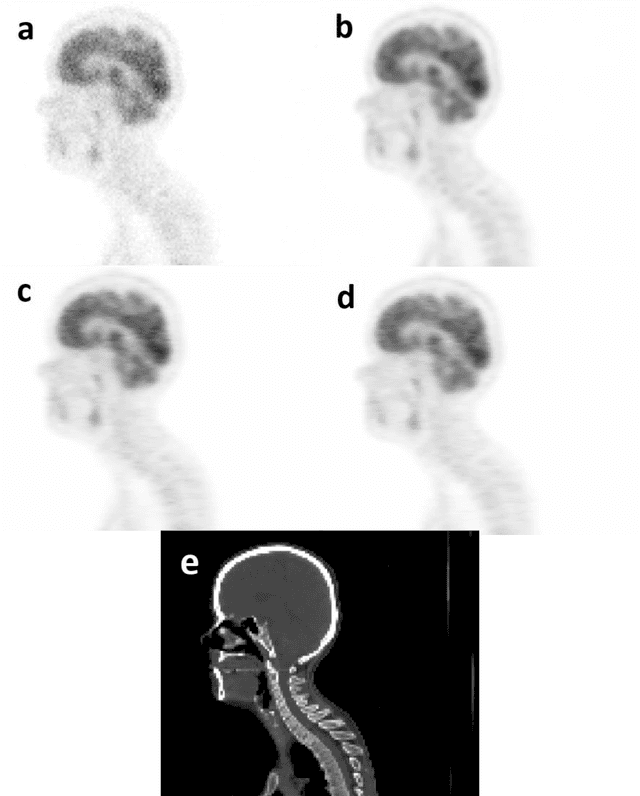

Reducing the injected dose would result in quality degradation and loss of information in PET imaging. To address this issue, deep learning methods have been introduced to predict standard PET images (S-PET) from the corresponding low-dose versions (L-PET). The existing deep learning-based denoising methods solely rely on a single dose level of PET images to predict the S-PET images. In this work, we proposed to exploit the prior knowledge in the form of multiple low-dose levels of PET images (in addition to the target low-dose level) to estimate the S-PET images.